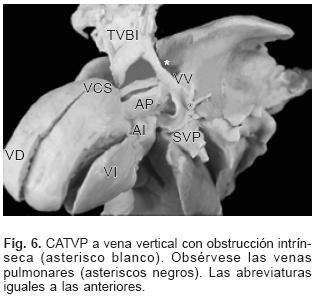

En todos los especímenes el SVP estuvo independiente, separado del atrio izquierdo y ubicado por detrás y un poco por encima de esta cámara cardíaca incompleta y pequeña (Figs. 1 y 2). El SVP se continuó con un vaso colector que siguió diferentes trayectos según el sitio de conexión anómala; en el tipo a vena cava superior el colector ascendió por detrás del bronquio derecho o del izquierdo según la posición de esa vena; en dos especímenes la obstrucción del colector fue intrínseca por estrechez del mismo en el sitio de su desembocadura (Figs. 3A y 4) y en un espécimen el colector siguió un trayecto anómalo entre la rama derecha de la arteria pulmonar y el bronquio derecho lo que provocó obstrucción extrínseca en el mismo (Fig. 3B). En el sitio de conexión anómala a la vena vertical el SVP recibió las venas de ambos pulmones y a través de un colector corto se continuó con la vena vertical ubicada del lado izquierdo, ésta a su vez lo hizo con el tronco venoso braquiocefálico izquierdo que desembocó en la vena cava superior y ésta en el atrio derecho (Fig. 5); en un espécimen existió obstrucción intrínseca en la vena vertical (Fig. 6).